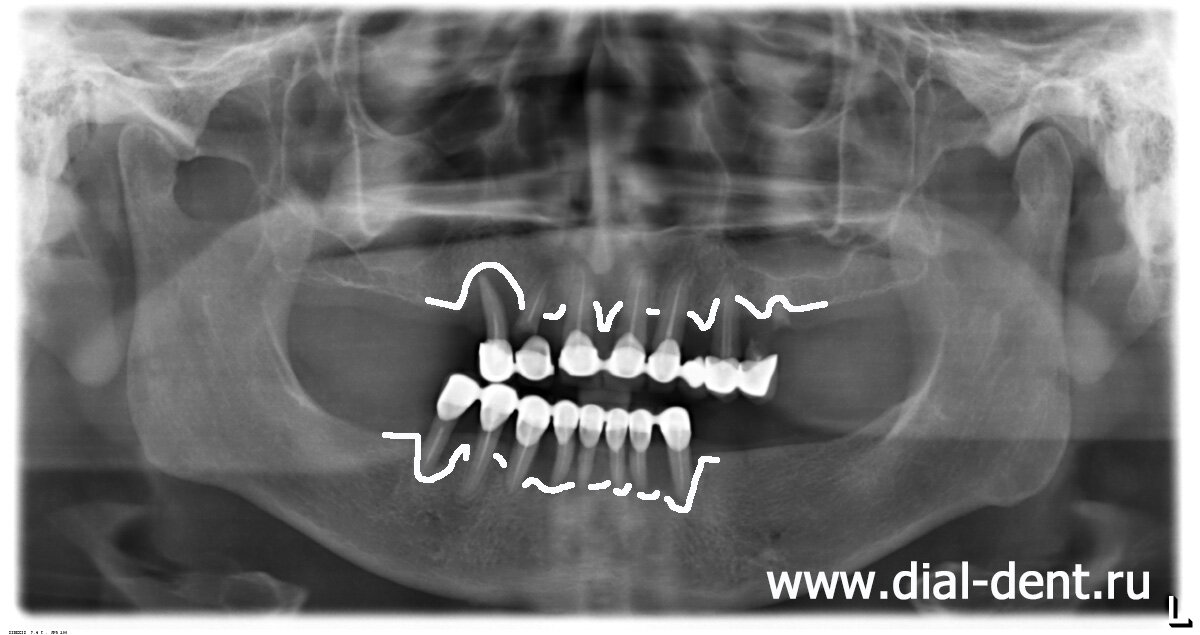

Женщина обратилась с жалобами на воспаление десен и боли в зубах. Все симптомы указывали на острый пародонтит. Чтобы оценить степень поражения нужен панорамный снимок, врачи должны выяснить, можно ли сохранить зубы или процесс принял необратимый характер. Перед удалением зубов врачи проводят тщательную диагностику. Диагностика показала, что ни один из 15 зубов нельзя сохранить. Десневые карманы очень глубокие, воспаление уничтожает костную ткань. На приведенном снимке схематично показан уровень кости.

из-за пародонтита снижен уровень кости